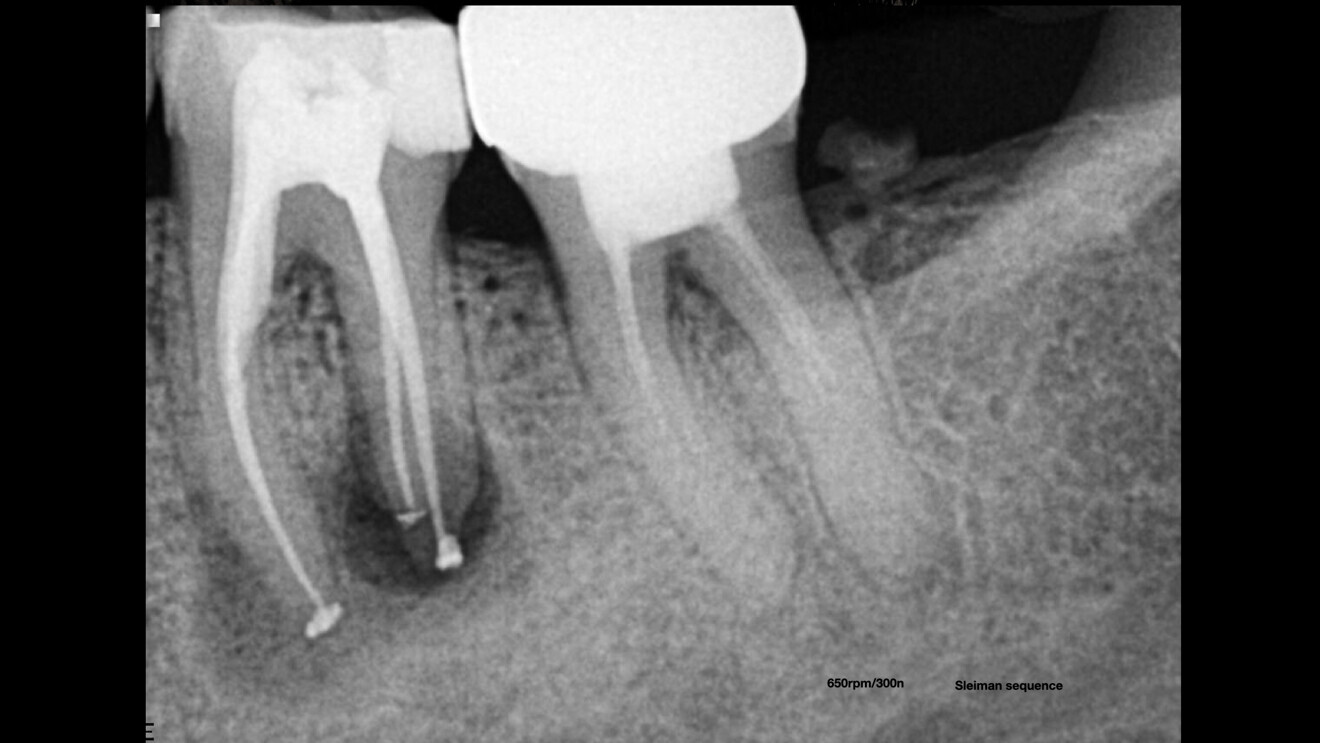

Starting with the diagnostic part, 3D imaging is an essential tool to complete the puzzle and find answers and to prepare a full treatment plan for a simple case as well as a complicated one. Artificial intelligence (AI) is a great addition regarding 3D imaging. For some time, I have been using the DTX Studio Clinic software, which has many AI features and enhanced image features that help me a great deal in my daily practice. When it is combined with the correct resolution and field of view for endodontics, it becomes a very powerful diagnostic tool. We recently upgraded our i-CAT unit to a DEXIS OP 3D unit, which has many advantages in the field of view and image quality, and it is just perfect when it is combined with the DTX software. Digital 3D imaging allows the discovery of unusual anatomy. In the case of a patient who presented complaining of pain and pressure on his tooth after undergoing root canal therapy some time before, careful reading of a CBCT scan of the area revealed a second canal in the central incisor and enabled us to locate the furcation (Figs. 1–3).

Figs. 1a & b: CBCT scan showing a second canal in the central incisor (E mode; field of view: 5 × 5 mm).

Fig. 3: Retreatment of the central incisor, after the shaping and obturation of both canals.